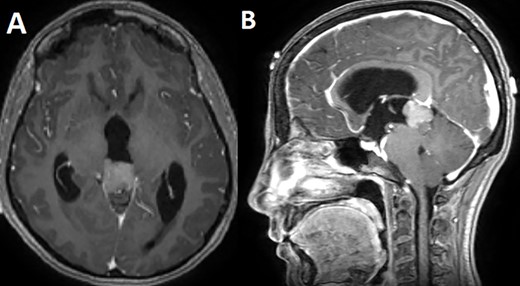

A 33-year-old lady presented to the clinic for bilateral retro-orbital headache with tinnitus most severe upon waking up in the morning for 3 months, without evidence of nausea, vomiting, or insomnia. Vital signs were within the normal range. The neurologic exam was non-focal. Enhanced brain magnetic resonance imaging (MRI) revealed a T1 hypointense, T2 hyperintense, homogenously enhancing Pineal tumor of 2 × 1.89 × 1.61 cm (anteroposterior × transverse × height) compressing the posterior wall of the third ventricle with evidence of moderate hydrocephalus (Fig. 1). The patient was scheduled for craniotomy for resection of the mass. In the operating room, an external ventricular drain was inserted in the right occipital horn followed by craniotomy and resection of the mass through a right occipital transtentorial approach. Gross total surgical resection was achieved under microscopic navigation (Fig. 2). The patient was extubated. Upon extubation the patient started to have chewing-like movement of her lips on the ET tube, afterward, she was transferred to the intensive care unit for monitoring. On postoperative day 1, we noticed that the patient was still having chewing-like movements typical of orofacial dyskinesia with evidence of buccal mucosal injury and swelling of the lips (Video 1). She was also complaining of inability to sleep. The patient was on regular postoperative medications (esomeprazole, cefazolin, paracetamol, morphine, dexamethasone, levetiracetam). An enhanced postoperative brain MRI was done for evaluation and confirmed complete resection of the lesion without any bleeding or ischemic changes (Fig. 3). The chewing like movements lasted for 72 hours and spontaneously resolved afterward. Pathology confirmed pineal parenchymal tumor of intermediate differentiation (WHO Grade III). The patient was treated with adjuvant radiotherapy. This is an unreported complication post pineal gland tumor resection in humans. Below we review the literature reporting abnormal facial movements associated with various pineal gland conditions as the data remains scarce concerning dyskinesia post pineal tumors resection in humans.

An intraoperative image under microscopic magnification showing the pineal tumor during the initial exposure (A) and the surgical cavity at the end of the gross total resection (B).